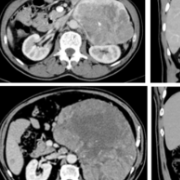

近期,医院收治的两名巨大肾上腺皮质腺癌患者中,一名68岁男性因“左腹疼痛1周”入院,检查显示患者左侧肾上腺约18×15cm巨大肿瘤侵犯肾门血管,手术难度极高。另一名56岁男性因“发现腹膜后肿物半年”入院,检查显示左肾上腺25×18cm巨大肿瘤同时累及左肾,并伴左肾静脉及下腔静脉癌栓形成,手术切除风险极大。

针对患者病情,李源教授团队联合血管外科、胆胰外科、麻醉科、代谢与内分泌科、重症医学科及肿瘤科等多学科专家进行会诊,制定了个性化手术方案。术中,团队精细操作,成功为第一例患者完整切除肿瘤及肾静脉并行左肾静脉重建术;为第二例患者实施左肾上腺巨大肿瘤切除术+左肾静脉癌栓取出术,耗时约4小时后完整切除肿瘤及癌栓,并成功为患者保留了左侧肾脏及其功能。两例患者术后均恢复顺利,后续计划至肿瘤科行下一步治疗。